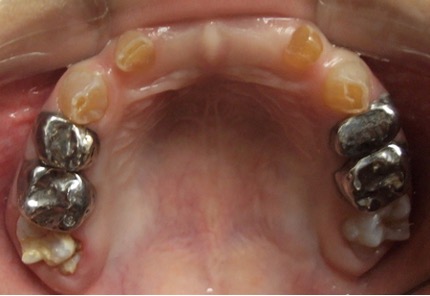

El examen clínico intraoral reveló alteración de la estructura y color de las piezas primarias, atrición y pérdida de la dimensión vertical (Figura 2). Radiográficamente se observó la presencia de coronas con marcada constricción cervical y raíces cortas (Figura 3). Presentaba alto riesgo cariogénico, por la presencia de lesiones de caries activas y dos restos radiculares, sumado a la anomalía estructural de la dentina (riesgo biológico específico) y bajo riesgo gingivoperiodontal. El riesgo socio-económico era alto por provenir de una familia con marcadas limitaciones económicas. Luego de la anamnesis, examen clínico y radiográfico, e interconsulta con el médico de cabecera se estableció el diagnóstico de DI Tipo I asociado a OI tipo I. Se planificó un tratamiento integral y preventivo con los objetivos de devolver forma y función, y proteger y evitar el desgaste de los tejidos conductas que pudieran interferir con el tratamiento.

Figura 2: Examen clínico intraoral del maxilar superior e inferior y vista anterior. Año 2007

En el año 2010, el mantenedor de espacio fijo superior se descementó, pero debido a la cercana erupción de los incisivos centrales superiores permanentes obser-vada radiográficamente (Figura 5), se decidió no recementarlo, confeccionando coronas de acero independientes en los 4 molares superiores primarios (5.4, 5.5, 6.4 y 6.5) y en el 7.5, previa restauración de las lesiones de caries con ionómero vítreo (Figura 6). Cuando se observó la erupción del 4.1 y 3.1, y de los 4 molares permanentes, se realizaron 3 aplicaciones de barniz de fluoruro de sodio al 5%, cumpliendo con los protocolos establecidos.

Figura 6: Postoperatorias clínicas maxilar superior e inferior año 2010.